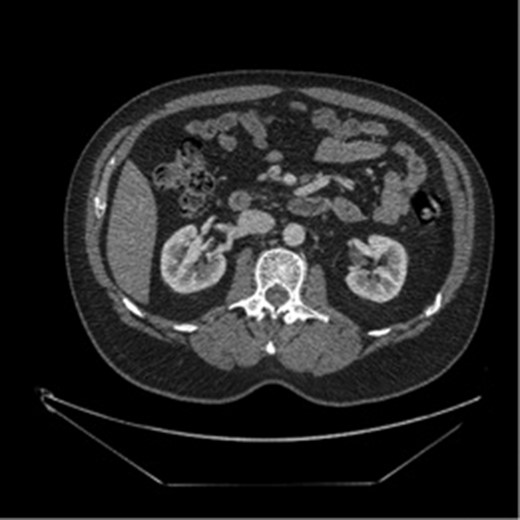

The patient was a 49-year-old male with history of hypertension presenting for evaluation for sudden onset of bilateral lower quadrant abdominal pain, nausea, emesis and non-bloody diarrhea starting 4 h prior to presentation. The patient denied prior abdominal surgeries, tobacco or illicit drug use. His history included hospitalization a year earlier for painless rectal bleeding, concerning for ischemic colitis, which was managed non-operatively. Current medications included Aspirin 81 mg and Valsartan-HCTZ. Physical exam revealed only mild left lower quadrant tenderness, and the labs values were quite unremarkable. A CT scan of the abdomen and pelvis with intravenous contrast demonstrated a thrombosed dissection, originating 2 cm from the ostium of the SMA with extension into the second and third order branches (Figs 1 and 2).

Initial imaging showing a thrombosed dissection, originating 2 cm from the ostium of the SMA with extension into the second and third order branches.